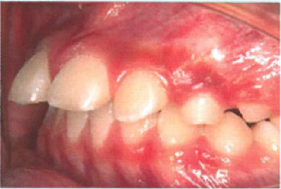

子ども歯ならび矯正法

プレオルソ

小児の骨が柔らかい時期にこそ 大きな効果が期待できる矯正法です。

マウスピース式の子ども歯ならび矯正法「プレオルソ」とは?

お子様への負担が少なく、費用的にも一般の矯正よりも始めやすいのが特徴です。

顎の成長を促し、歯ならびだけでなく口呼吸の改善、また将来の成人矯正の回避も期待できるなど多くのメリットがあります。

骨の柔らかい時期に始めると効果が高い

永久歯に生え変わってからでは、全ての歯にギラギラした装置をつけるいわゆる「本格矯正」になりますが、この治療法であれば小児(6才~10才)の骨の軟らかい時期に使うことで、非常に大きな効果が期待できます。